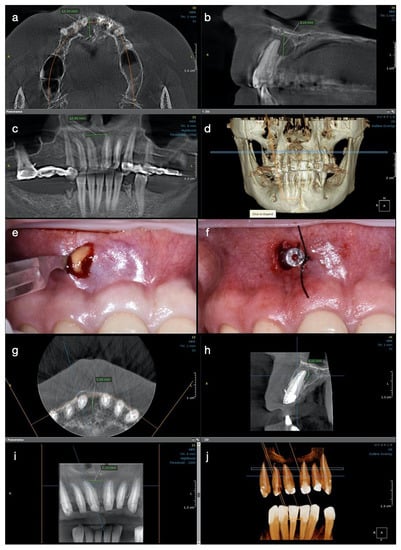

A CBCT investigation was recommended for the upper anterior teeth and performed in the dental clinic with the following parameters: 8 × 15 cm field of view, 250 µm voxel size, 90 kV, 7.1 mA, and 8.14 s emission. On the CBCT images analyzed on the 25” Dell monitor with a 1920 × 1080 pixel resolution, a large unilocular radiolucent lesion which involved the periapical region of tooth #11 was observed, extending towards the mesial region. It exceeded the middle maxillary line and was also involving the mesial part of the apical root third of tooth #21. In an upper direction, it was extending to the nasal fossa, presenting an intact nasal floor.

The size of the lesion was measured using the measurement tools of OnDemand3D (OP 3D™ Pro, KaVo Dental GmbH) and was about 15 mm in height, 13 mm in the buccolingual direction, and 13 mm in the mesiodistal. The lesion appeared well contoured by a thin radiopaque border line on all its contours, communicating with the apex of tooth 11 in its inferior part (presumptive diagnosis of pocket cyst) (Figure 2a–d). In addition, on the CBCT scan, teeth #21 and 22 appeared to be endodontically treated, with a radio-opaque obturation material present in the root canal space, 3 mm shorter from the radiographic apex for tooth #21 and 2 mm shorter for tooth #22. A small area of radiolucency of about 1 mm diameter around the apex of tooth #22 was also observed.

From the history, clinical and para-clinical examination, a diagnosis of pulpal necrosis complicated with a cyst-like periapical lesion was established for tooth #11. Teeth #21 and 22 had previously been endodontically treated, with the infra-obturation of the root canal system. Considering the complex prosthetic rehabilitation that followed and the endodontic and periapical status, the decision of an endodontic treatment for tooth #11 was taken, with monitoring of the evolution of the lesion and orthograde endodontic retreatment for teeth #21 and 22. The treatment plan was explained to the patient, and her informed consent was taken.

For teeth #21 and 22, endodontic orthograde retreatment was performed in a single visit later on, but no intracanal medication was used. Teeth #12 and 13 were also endodontically treated in one appointment for prosthodontic reasons, after the abutment’s preparation.

At the three-month follow up, the buccal bone in the central incisor’s area became consistent at palpation, and the patient described no symptoms during this period of time or at the clinical exam. At the 6-months control, the patient was subjected to another CBCT investigation. A significant reduction in the size of the periapical lesion in a buccolingual direction, from 12 mm to 5.88 mm, and in a mesiodistal direction, from almost 13 mm to 7.70 mm, was observed with the continued increase in density of the new trabecular bone in all three plans (Figure 2g–j). The total height of the lesion was reduced from 8.26 mm to 5 mm, and the cortical buccal plate appeared significantly wider and mineralized.

The postoperative CBCT scan at 12 months revealed the continuous formation of the bone, while the lesion continued to heal, remineralization was observed buccally around the entire root contour, and the palatal radiolucency was also decreased, with the observation of an increased bone regeneration activity and more trabeculae filling the lesion (Figure 3a–d). Both CBCT investigations performed at recall had the same characteristics: 5 × 5 cm field of view, 85 µm voxel size, 90 kV, 6.3 mA and 8.70 s emission, and were analyzed with the same program (OnDemand3D, KaVo Dental GmbH) on the same computer screen as the initial one. At present, the patient is still symptom-free and another clinical and radiological control will follow at 18 months.

Figure 2. Case 2. Radiological investigations and clinical images of tooth #11: (ad) Initial CBCT scans with the measurements of the lesion size: 12.10 mm in buccolingual direction, 8.26 mm in height, and 12.49 mm mesiodistal diameter, with the buccal cortical plate resorbed (12.10 × 8.26 × 12.49 mm); (e,f) The surgical procedure of decompression at the end of the endodontic treatment with the appearance of yellow fluid draining from the lesion, and the drainage tube fixed with sutures on the mucosa; (gj) CBCT scans and the 3D reconstruction at 6 months after the endodontic therapy, with the formation of new bone and increased reduction of the lesion size, starting from its periphery (5.88 × 5.10 × 7.70 mm).

Figure 3. Case 2. CBCT scan for tooth #11 at the one-year control: (a) The buccal cortical plate is completely restored, and new bone trabecula can be observed; (b) The lesion looks almost completely healed buccally and with a significant reduction in size palatal and height; (c) newly formed bone now occupies the cavity of the former lesion; (d) the 3D reconstruction shows the quality of the endodontic treatments on all upper frontal teeth.